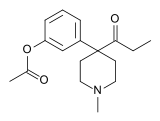

Ketobemidones

Structures